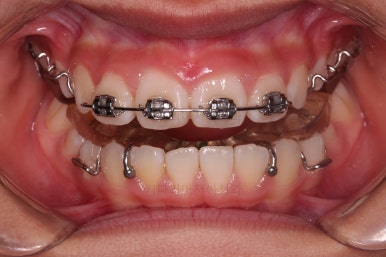

부산소아교정 초진 시 입안의 모습입니다.

윗니가 아랫니보다 많이 앞에 나와있고요.

심지어는 틈새가 벌어지기까지 했습니다.

윗니가 배열 되어있는 U자 형태(그릇 형태)가 아랫니보다 좁은 양상이고요.

이런 앵글씨 2급 부정교합에서는 아랫니가 윗니와 만나기 위해 솟구쳐서 과개교합(아래 앞니가 윗니 뒤쪽으로 깊숙히 올라가 있는 상태)이 나타나기까지 합니다.

트윈블락 장치와 더불어 윗니 앞니는 가지런하게 하기 위해서 브라켓-철사 장치가 부분적으로 들어갔는데요.

아래턱이 성장하기 위해서 너무 삐뚠 윗니 앞니는 아래턱이 앞으로 나오는 걸 방해하기 때문에 부분적으로 부착형 장치를 쓸 수 밖에 없는 상황이었습니다.

윗니에 들어가는 장치는 악궁확장 기능도 들어가 있어서 위턱을 넓히며 아래턱을 앞으로 내어주는 3차원적인 조절이 가능했습니다.